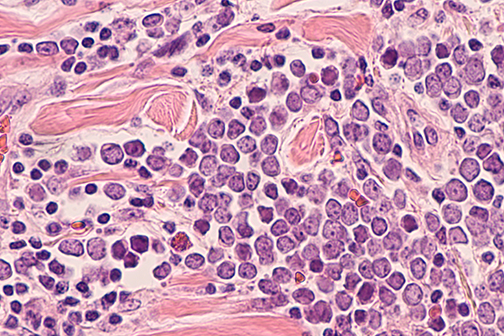

LSU Health Research Suggests A New Approach For Treatment-Resistant Breast Cancers

A collaborative study between LSU Health New Orleans School of Medicine, the University of Rochester and Cellestia Biotech AG, a biopharmaceutical company headquartered in Basel, Switzerland, provides compelling evidence that combining an investigational oral drug with standard-of-care medications reverts hormone resistance and increases Rx effectiveness in experimental models of estrogen-receptor positive (ER+) and triple-negative breast cancers (TNBC), respectively. More